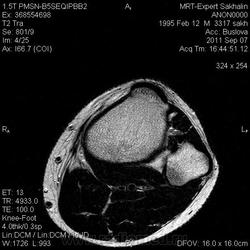

МРТ коленного сустава.Остеома малоберцовой кости?

Сегодня был молодой человек без направления.Принес диск КТ-исследования  коленных суставов от 2010 года.Заинтересовала малоберцовая кость.

И клиника какая? Болезненность есть? По МР-сигналу если все вышеизложенное исключается больше данных за остеохондрому, (экзофитное расположение, сигнальные характеристики костного мозга)

Не знаю-может быть и вариант строения.Но правая малоберцовая кость не изменена.Кортикальный слой не нарушен.Как мне показалось-по сравнению с КТ-исследованием без динамики.

Склоняюсь к остеохондроме.

КХЭ с неоартрозом с большеберцевой костью и деф. артрозом в этом суставе...  Но экзостозы обычно множественные...

Нет, Анатолий Владимирович, экзостозы чаще солитарные. По МКБ "остеохондрома" и "множественные костно-хрящевые экзостозы" вообще разные нозологии.

Касательно данного случая. Думаю - остеохондрома.

Тем не менее, настоятельно призываю коллег придерживаться общепринятых (и у нас, и у буржуев) стандартов диагностики заболеваний костей. Согласно которым, основным методом диагностики является обычная рентгенография. КТ- очень полезный дополнительный метод. МРТ - дополнительный метод, имеющий более узкие показания. МР-семиотика опухолей костей в достаточной мере не разработана, поэтому в костной патологии не стоит делать заключения только по МРТ, без данных рентгенографии или КТ